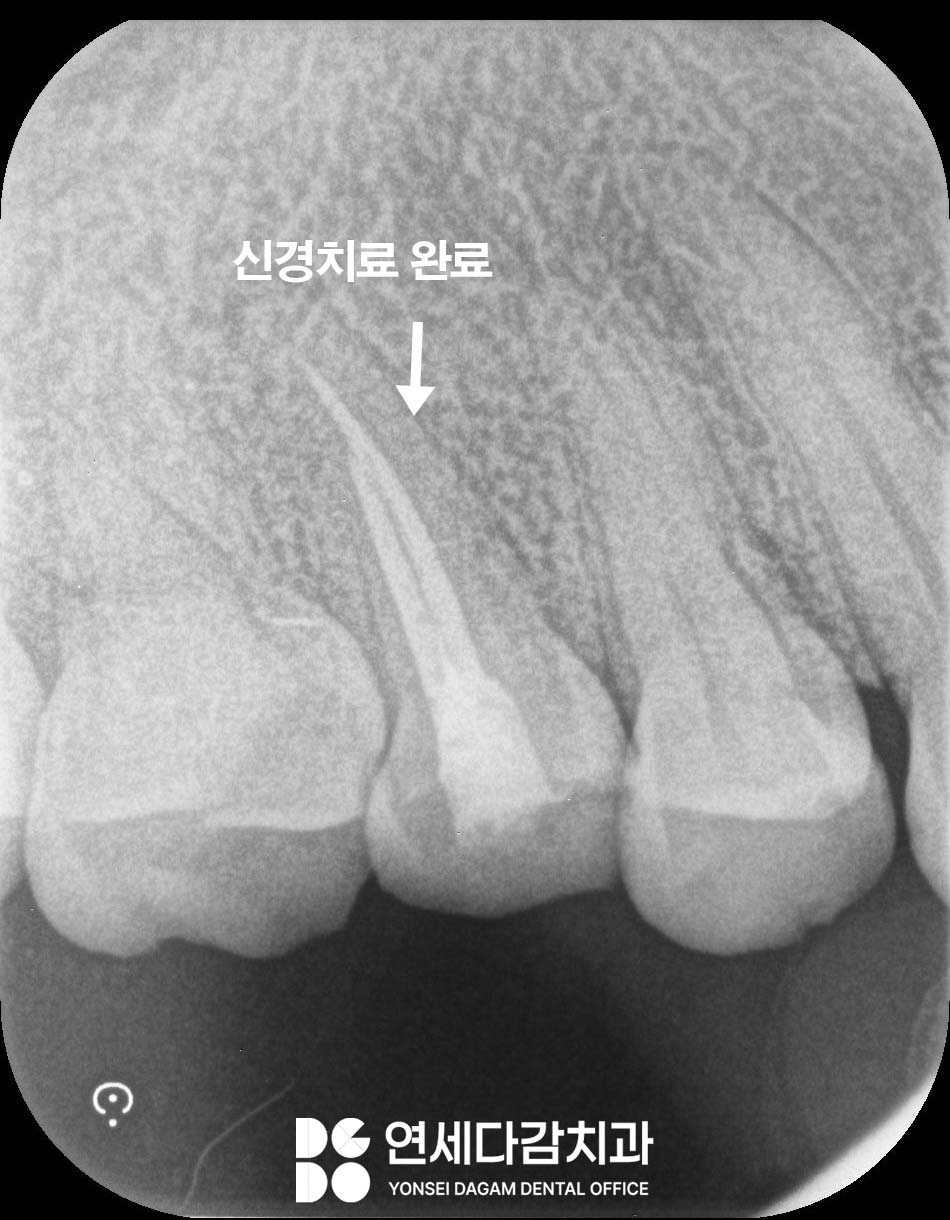

근관치료 과정에서 치아 내부에서도

송파역 치과 에서 표시한 것처럼

균열선이 발견된 것을 볼 수 있습니다.

신경 치료 후 크라운이

꼭 필요한 이유

근관 치료를 받으면 통증은 사라지지만,

치료가 다 끝난 것은 아닙니다.